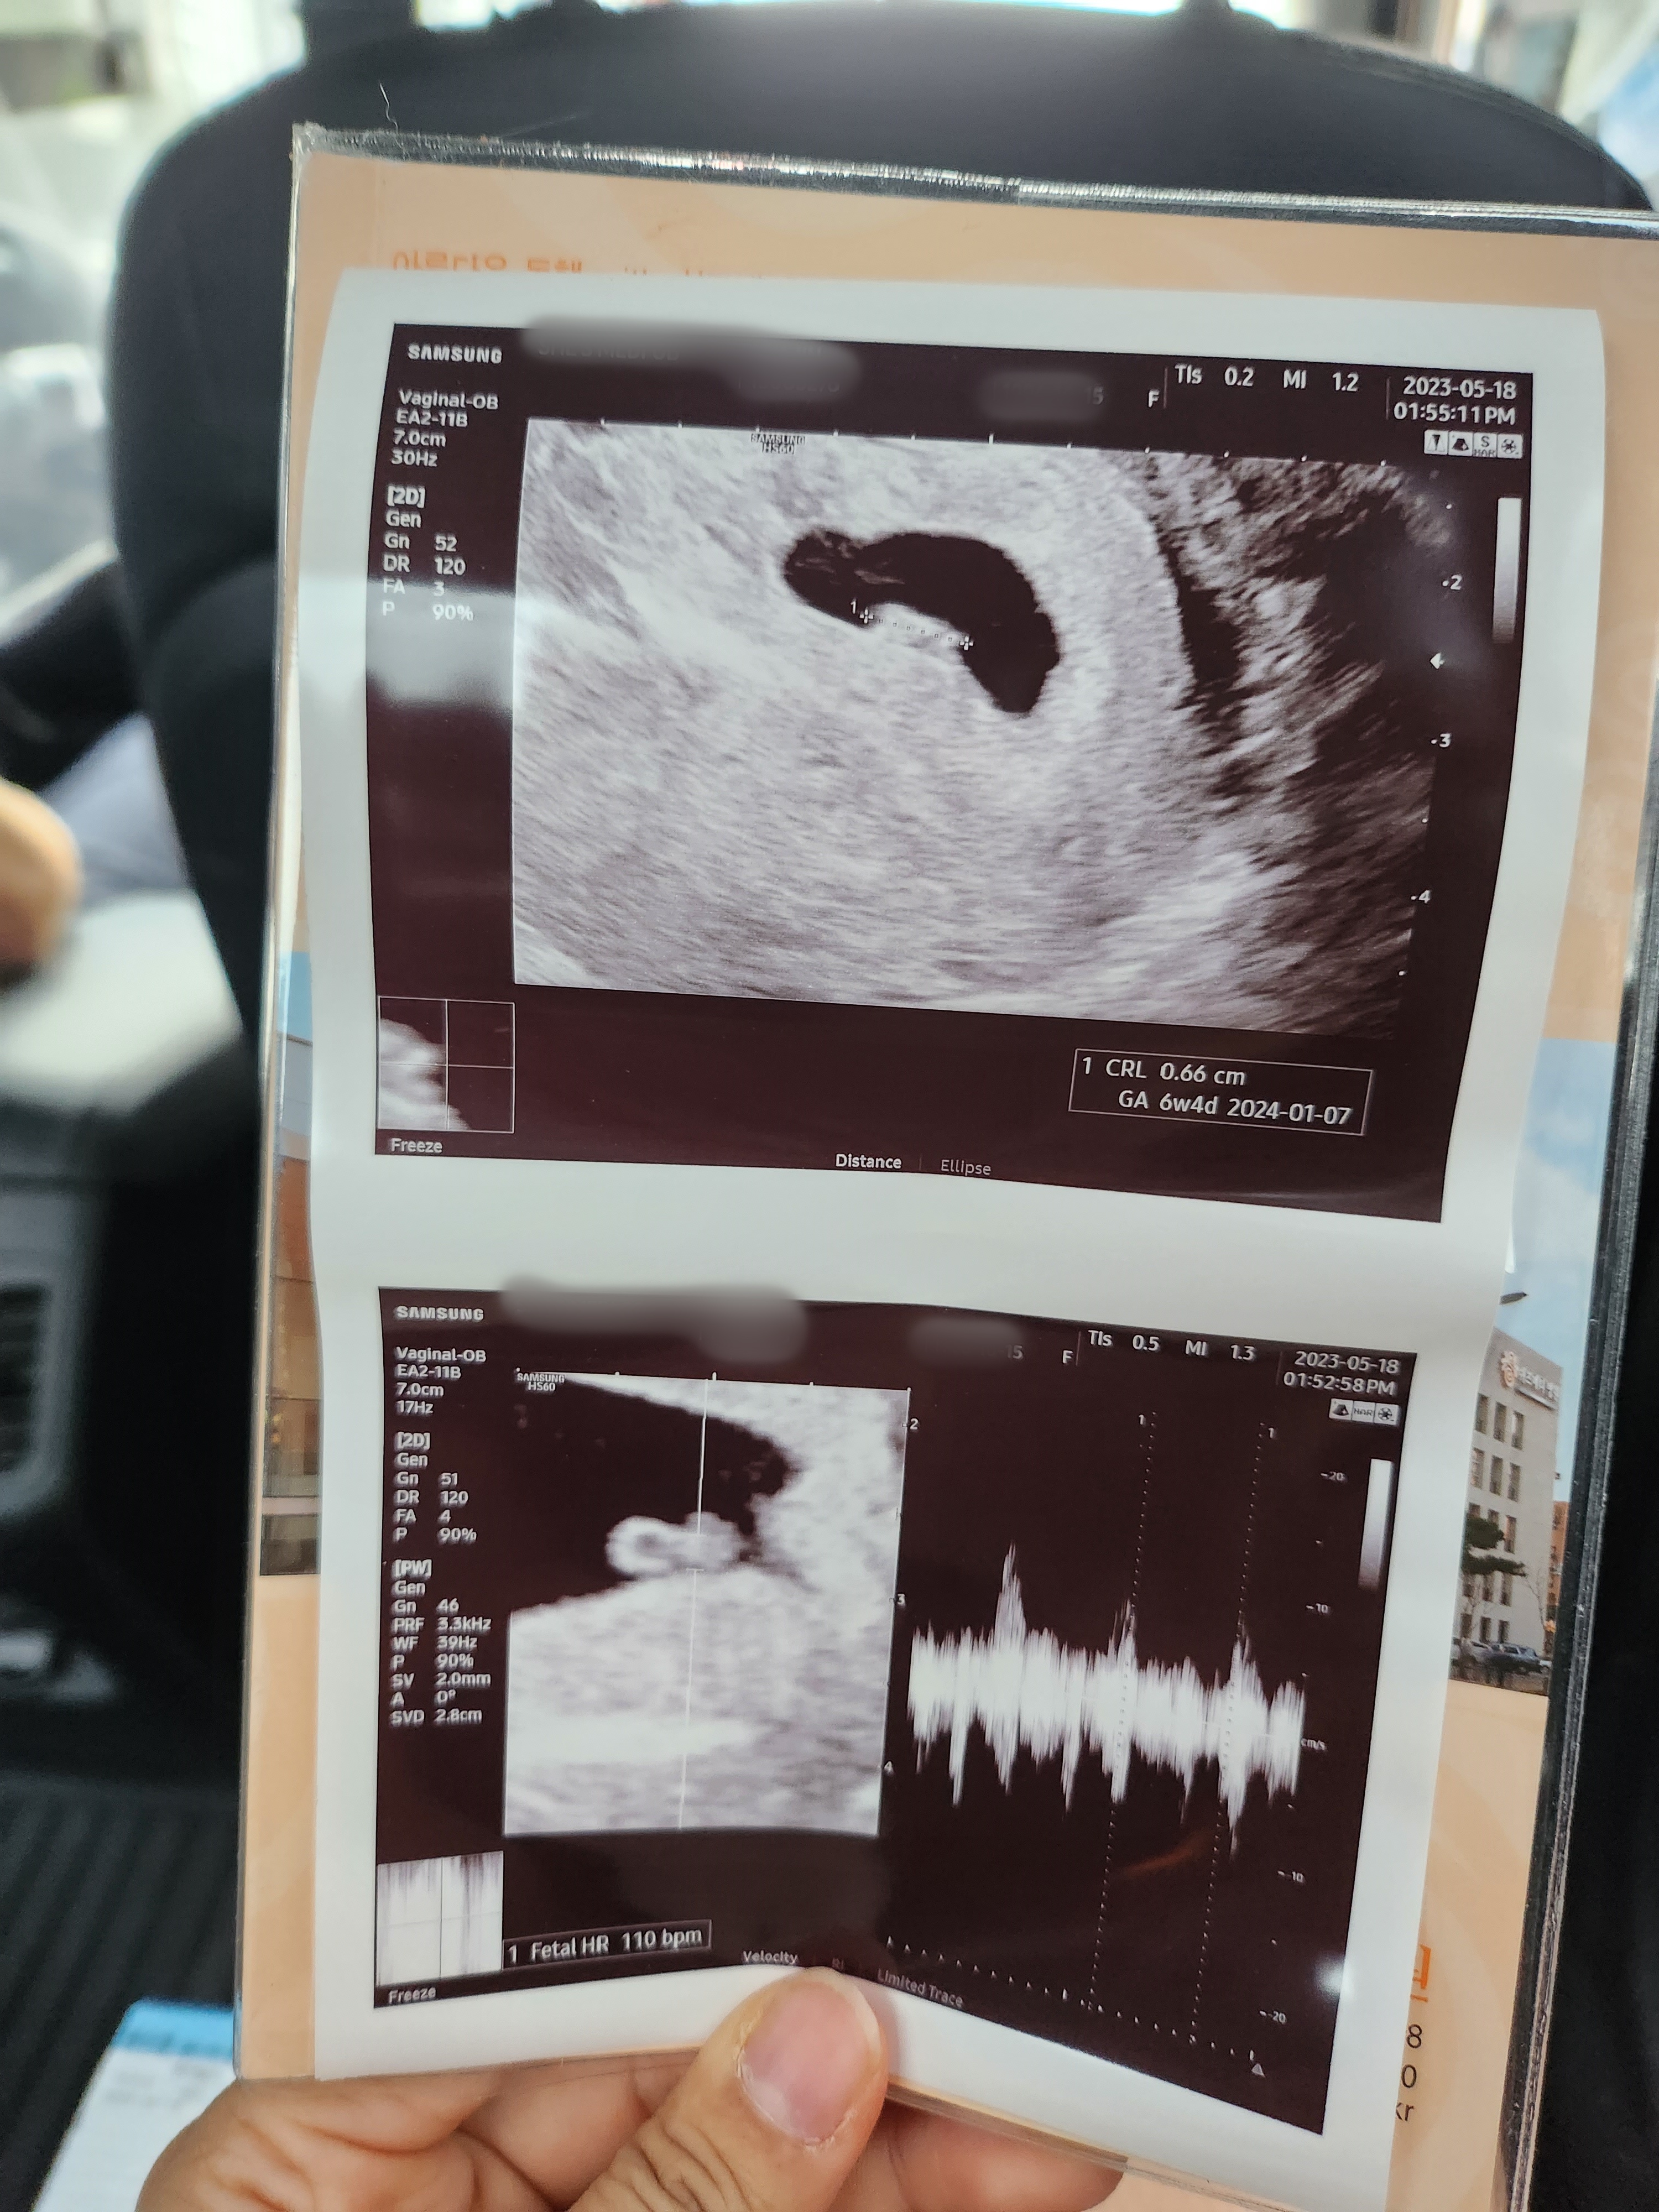

-7주차-

난황 옆에 작은 아기가 생겼다.

주수보단 살짝 작았지만 선생님이 이정도는 다음주에 따라잡으면 된다고 하셨다.

심장이 반짝반짝 뛰는 모습도 봤다.ㅎㅎ

심장소리는 들려주시더니 뛰기 시작한 지 얼마 안 된 것 같다고 하시며

다음 주에 잘 뛰고 있으면 되니까 8주차에 보자고 하셨다.

초음파를 보는데 토끼띠인걸 티 내고 싶은 건지 완벽한 토끼모양이었다.ㅎㅎ

이건 너무 귀여운 거 아닌가?!ㅎㅎ

그리고 한 가지 안 좋은 소식이 생겼다.

피고임이 갑자기 크게 생긴 것..

내가 무리했나..

한 번 스크린골프를 쳤는데 그게 문제였을까.. 걱정이 크게 생겼다.

선생님께선 일주일 동안 질정을 처방해 주시며 누워서 푹 쉬라고 괜찮을 거고 다음 주에 보자고 하셨다.